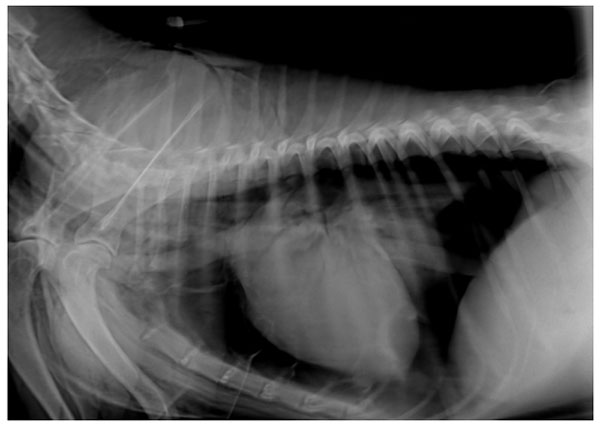

Βλέποντας μέσα από σκιές. Ακτινολογία θώρακος σκύλου και γάτας

Το διαδικτυακό αυτό σεμινάριο αφορά την αναγνώριση της φυσιολογικής ανατομίας του θώρακα και το βασικό τρόπο ανάγνωσης ακτινογραφιών. Θα συζητηθούν με παραδείγματα, η αναγνώριση και ερμηνεία των πνευμονικών προτύπων καθώς και ανωμαλίες του μεσοπνευμονίου και της πλευριτικής κοιλότητας. Με την ολοκλήρωση του σεμιναρίου οι συμμετέχοντες θα: Αναγνωρίζουν τη φυσιολογική ακτινολογική ανατομία του θώρακα Καταλάβουν τον τρόπο που διαβάζουμε μια ακτινογραφία Μπορούν να αναγνωρίσουν τα πνευμονικά πρότυπα, τη χρήση τους και τους περιορισμούς τους Εξοικειωθούν με συχνές ανωμαλίες του μεσοπνευμόνιου και της πλευριτικής κοιλότητας